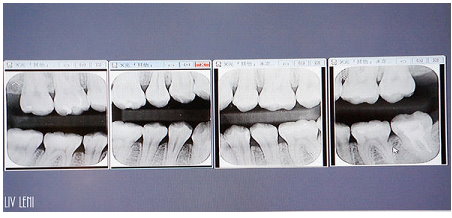

由於我是 輕微的牙齦炎,X光片 出來的結果也良好,

我的全口牙周囊袋測量數值,前面牙齒都是3釐米,

越後面的牙齒有4、5釐米的深度,

有2顆更誇張,直逼7和8釐米(右下與左下最後一顆)

越後方的牙齒越難清潔,

因此通常我的囊袋在最後幾顆牙齒都較深><

至於位在深層,牙根周圍、齒槽骨遭破壞的程度,

就需用全口X光檢查透視。

前排牙齒變得更健康了,從原本的3釐米,變成2釐米,

後面囊袋4、5、7、8釐米的深度,都恢復成3釐米了!!